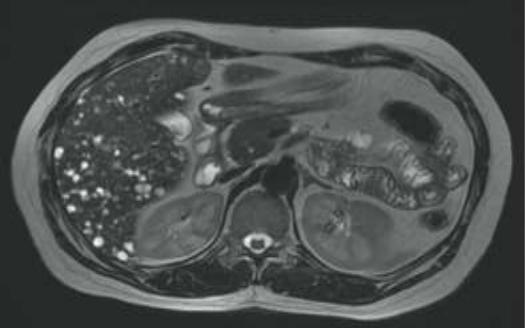

Analise a imagem de ressonância magnética ponderada em T2 e assinale o diagnóstico mais provável:

Enunciado 3029427-1